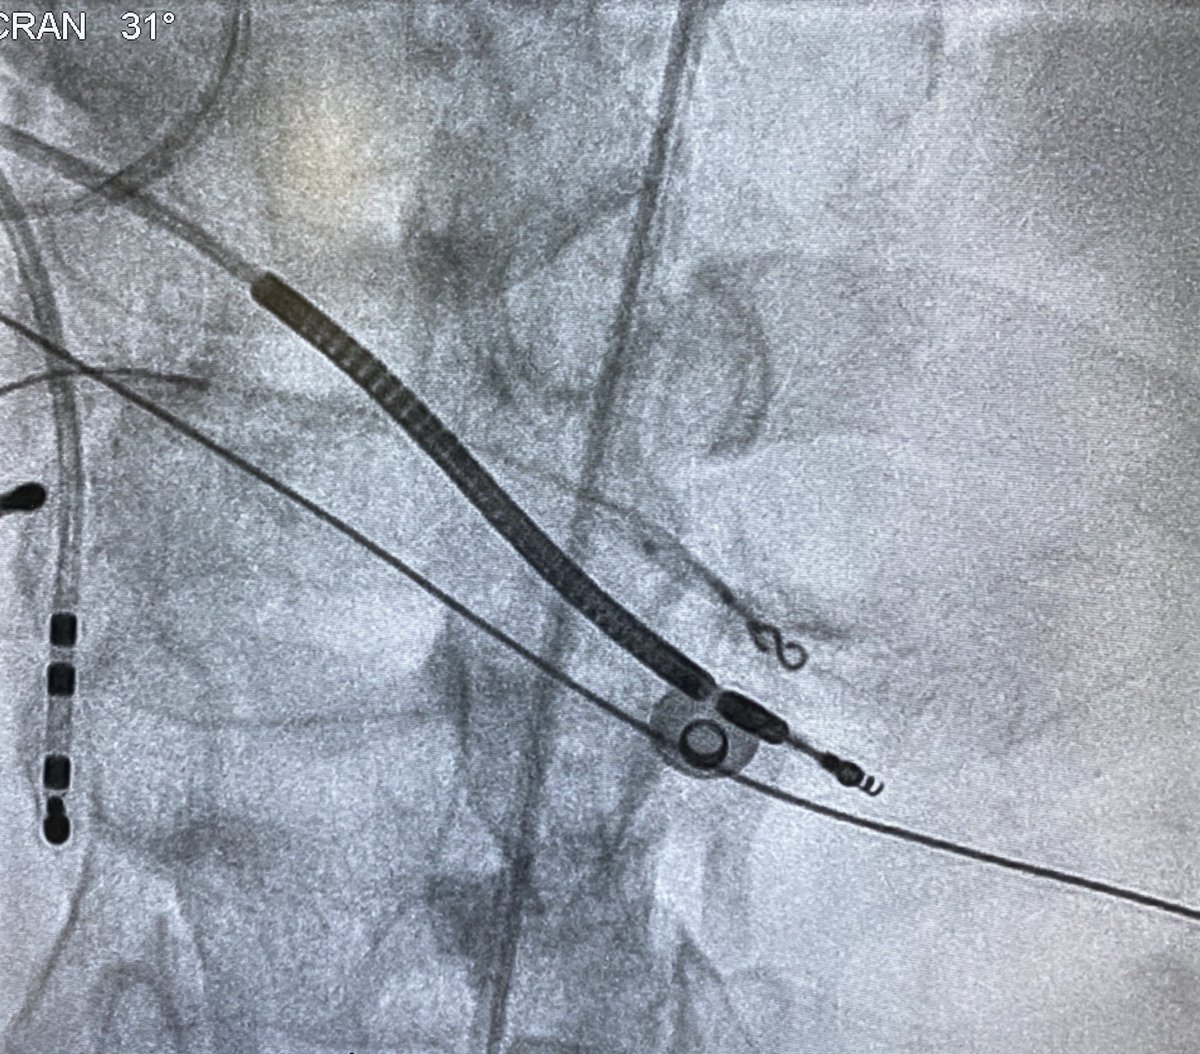

Murphy Lyu Sachin Vadodaria Kevin Brady Jeff Zhang M Abbott Cardiovascular This was the septal VT from today, Murphy. No maps since we’d mapped it previously. First pic shows termination with cold saline in RPDA. Wire mapping shows concealed entrainment with TCL-PPI of zero. Coiling+gel foam in distal RPDA renders VT uninducible

<a href="/murphy_lzy/">Murphy Lyu</a> <a href="/sachinjv/">Sachin Vadodaria</a> <a href="/Hapa_EP/">Kevin Brady</a> <a href="/JeffZhanghk2017/">Jeff Zhang</a> <a href="/Mya49099911/">M</a> <a href="/AbbottCardio/">Abbott Cardiovascular</a> This was the septal VT from today, Murphy. No maps since we’d mapped it previously. First pic shows termination with cold saline in RPDA. Wire mapping shows concealed entrainment with TCL-PPI of zero. Coiling+gel foam in distal RPDA renders VT uninducible